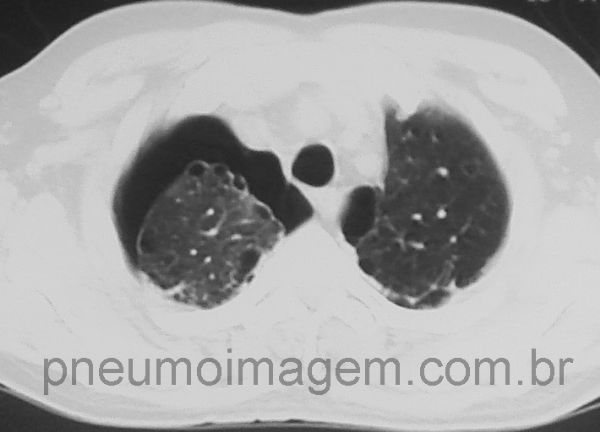

Pneumotórax espontâneo à direita em fumante.

Observe as blebs subpleurais, causa da doença.

Neste corte se observa que as blebs também existem no pulmão esquerdo, com risco futuro de pneumotórax.